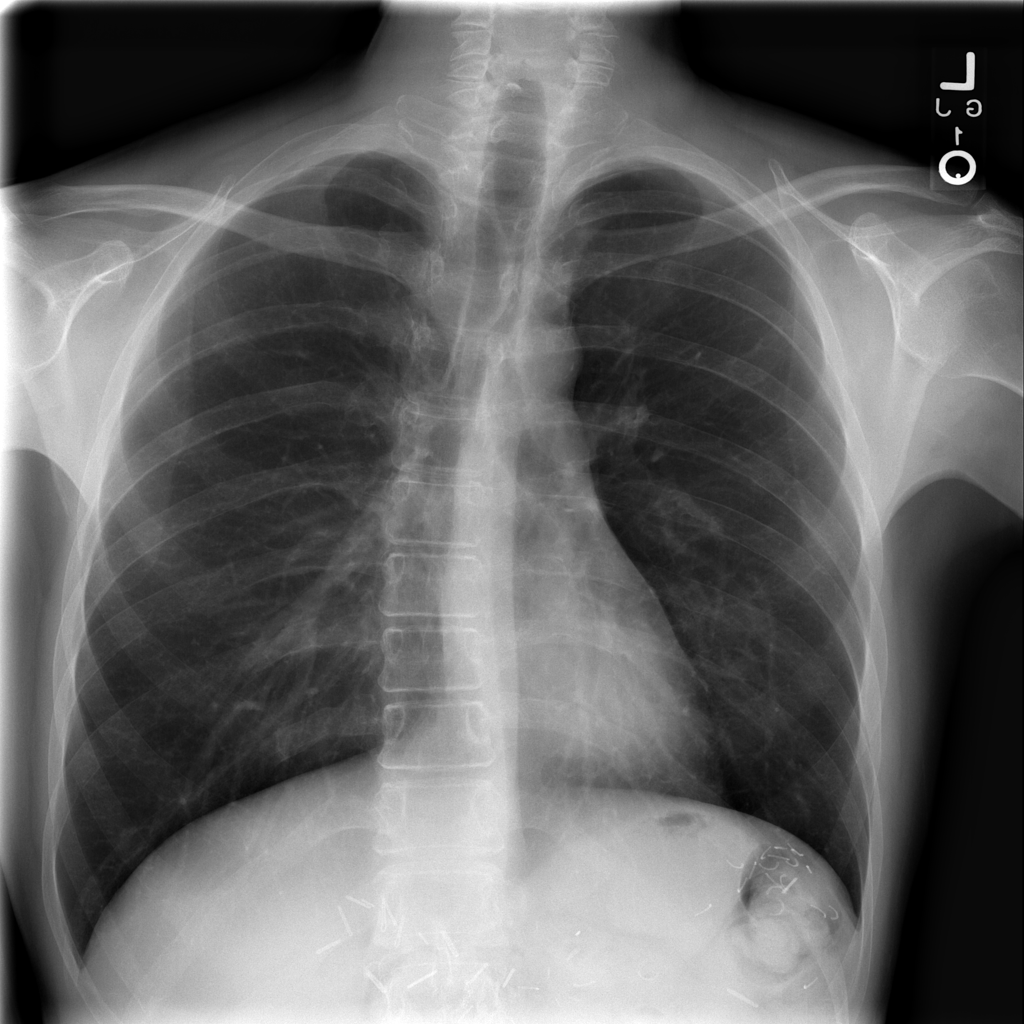

PAT-50E5 · IMG-001Pneumothorax

PAT-50E5 · IMG-001

AP